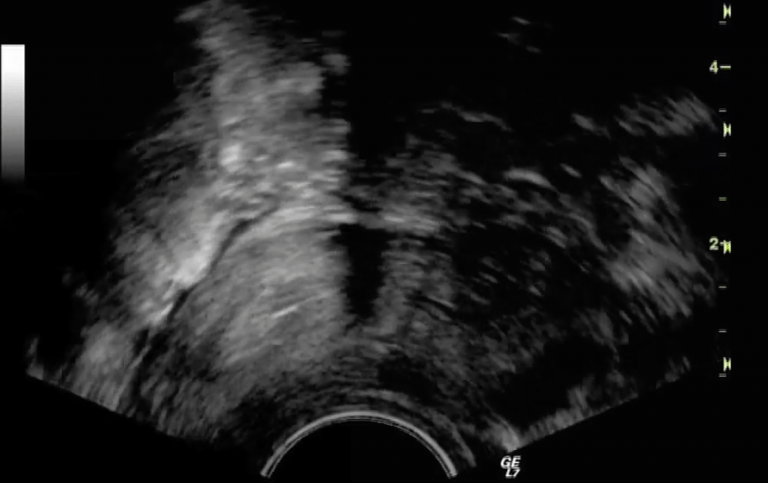

Undersøkelse av livmorhule og eggledere ved utredning av ufrivillig barnløshet

Som en del av utredningen av ufrivillig barnløshet undersøker vi normalt om det er noe galt inne i livmorhulen eller...